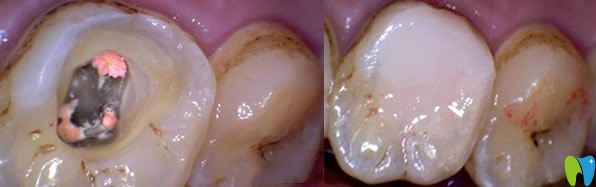

一、急性牙髓炎如何治療?

急性牙髓炎主要是細(xì)菌感染引起牙髓組織的急性炎癥,遇冷更加疼痛。急性牙髓炎發(fā)病急,疼痛劇烈,牙齦紅腫、化膿等癥狀,一般鎮(zhèn)痛藥物效果不明顯,遇到良心牙醫(yī)會(huì)保存活髓及患牙,利用開髓及藥物來緩解疼痛,服用消炎藥兩到三天,疼痛緩解后,嚴(yán)重的牙髓炎可采取根管治療或者活髓切斷術(shù),能夠及時(shí)預(yù)防病情嚴(yán)重及擴(kuò)散。沒有保存價(jià)值的牙齒可拔掉。

急性牙髓炎治療方法